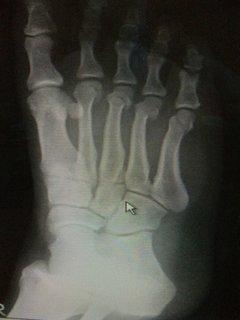

今日こんなおもろい写メが送られてきた☆

よく見なわからんかな・・・(p_-)実は、これ・・・親指以外残り4本全部折れてるねんで・・・(^_^;)サーフィンしてない友達やねんけど、お互い骨つながりで、どぉ~や?痛い??って、いたわりあってる☆

なんで、4本も折れたのか??バイク乗ってて事故られたらしい。よっぽどの事故やったんやな?

病院で「順調です。」って言われたらしいけど、何が順調なんかがさっぱりわからん・・・って言ってた。普通にまだ痛いんやろう(^・^)ほんで、もうすぐなんか装置をつけられるら・し・い・・・(笑)ってさ(^_^)v

わかる???装置やで!!!さちの事思い出した???(笑)この肩の装置・・・2万近くやったよね~☆足の指、4本分って滅多にないし、またこれ、特殊な装置なんちゃうの~??おもろいっ!!受付でべラボ~な金額言われて、目ん玉飛び出すか、気絶するか、2択好きなん選んでや~(^O^)/